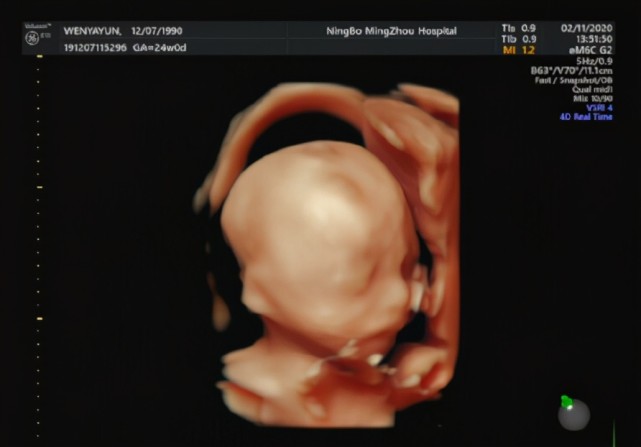

这个孕周段有个重要的产检,叫“排畸B超”。

有的医院是做普通B超进行排畸,有的医院是做四维排畸。

有的医院做一次排畸B超,在孕20-24周做,有的医院做两次排畸B超,孕20-24周做一次,到了孕28周会再做一次。

因为 这1-2次B超都是排查胎儿的重大畸形,准爸爸就更不能缺席了,一定要陪在孕妈身边。

有的医院检查时,准爸爸是可以陪着进去的,那检查时,医生会告诉准爸妈胎儿的各个身体部位,那准爸爸就更不要错过和胎宝宝的第一次见面啦!

普通B超(三维)也完全可以起到排畸的效果,只是四维B超可以算是宝宝的第一张照片,比较有意义;